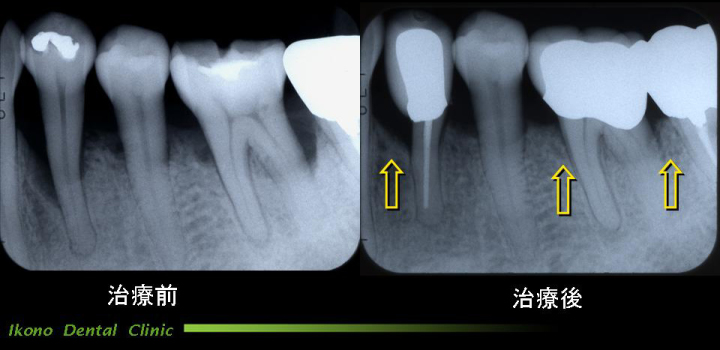

歯内治療

むし歯などによって歯髄(歯の中の神経や血管などの組織のことで、一般に神経と説明されている。) まで感染を起こしている場合、感染した歯髄を取り除いて治療することを歯内治療といいます。

歯髄の入っているトンネルは左の図のように、曲がっていたり、複雑にいりくんでいることが多く、細菌や汚染物質を完全に除去することは容易ではありません。

治療がうまく行かず、再発した場合、今度は歯の外側で、炎症(一般的に化膿していると説明される)が起こります。

こうなると噛んだら痛い、歯茎が腫れる、歯が浮いたような感じがするといった症状が出ます。

そうすると再治療が必要になりますが、再治療はさらに時間がかかるだけでなく、むずかしい治療になります。

歯の根の治療

当院の治療例クリックで拡大

歯内治療は患者さんにとって、見えないところにもかかわらず、時間や回数がかかり楽な治療ではありません。 けれども、なるべく再発しないよう、信頼できる歯科医で、最後までしっかり治療することが大切です。

また、治療したあとは再発していないか定期的にレントゲンで確認することをお勧めします。